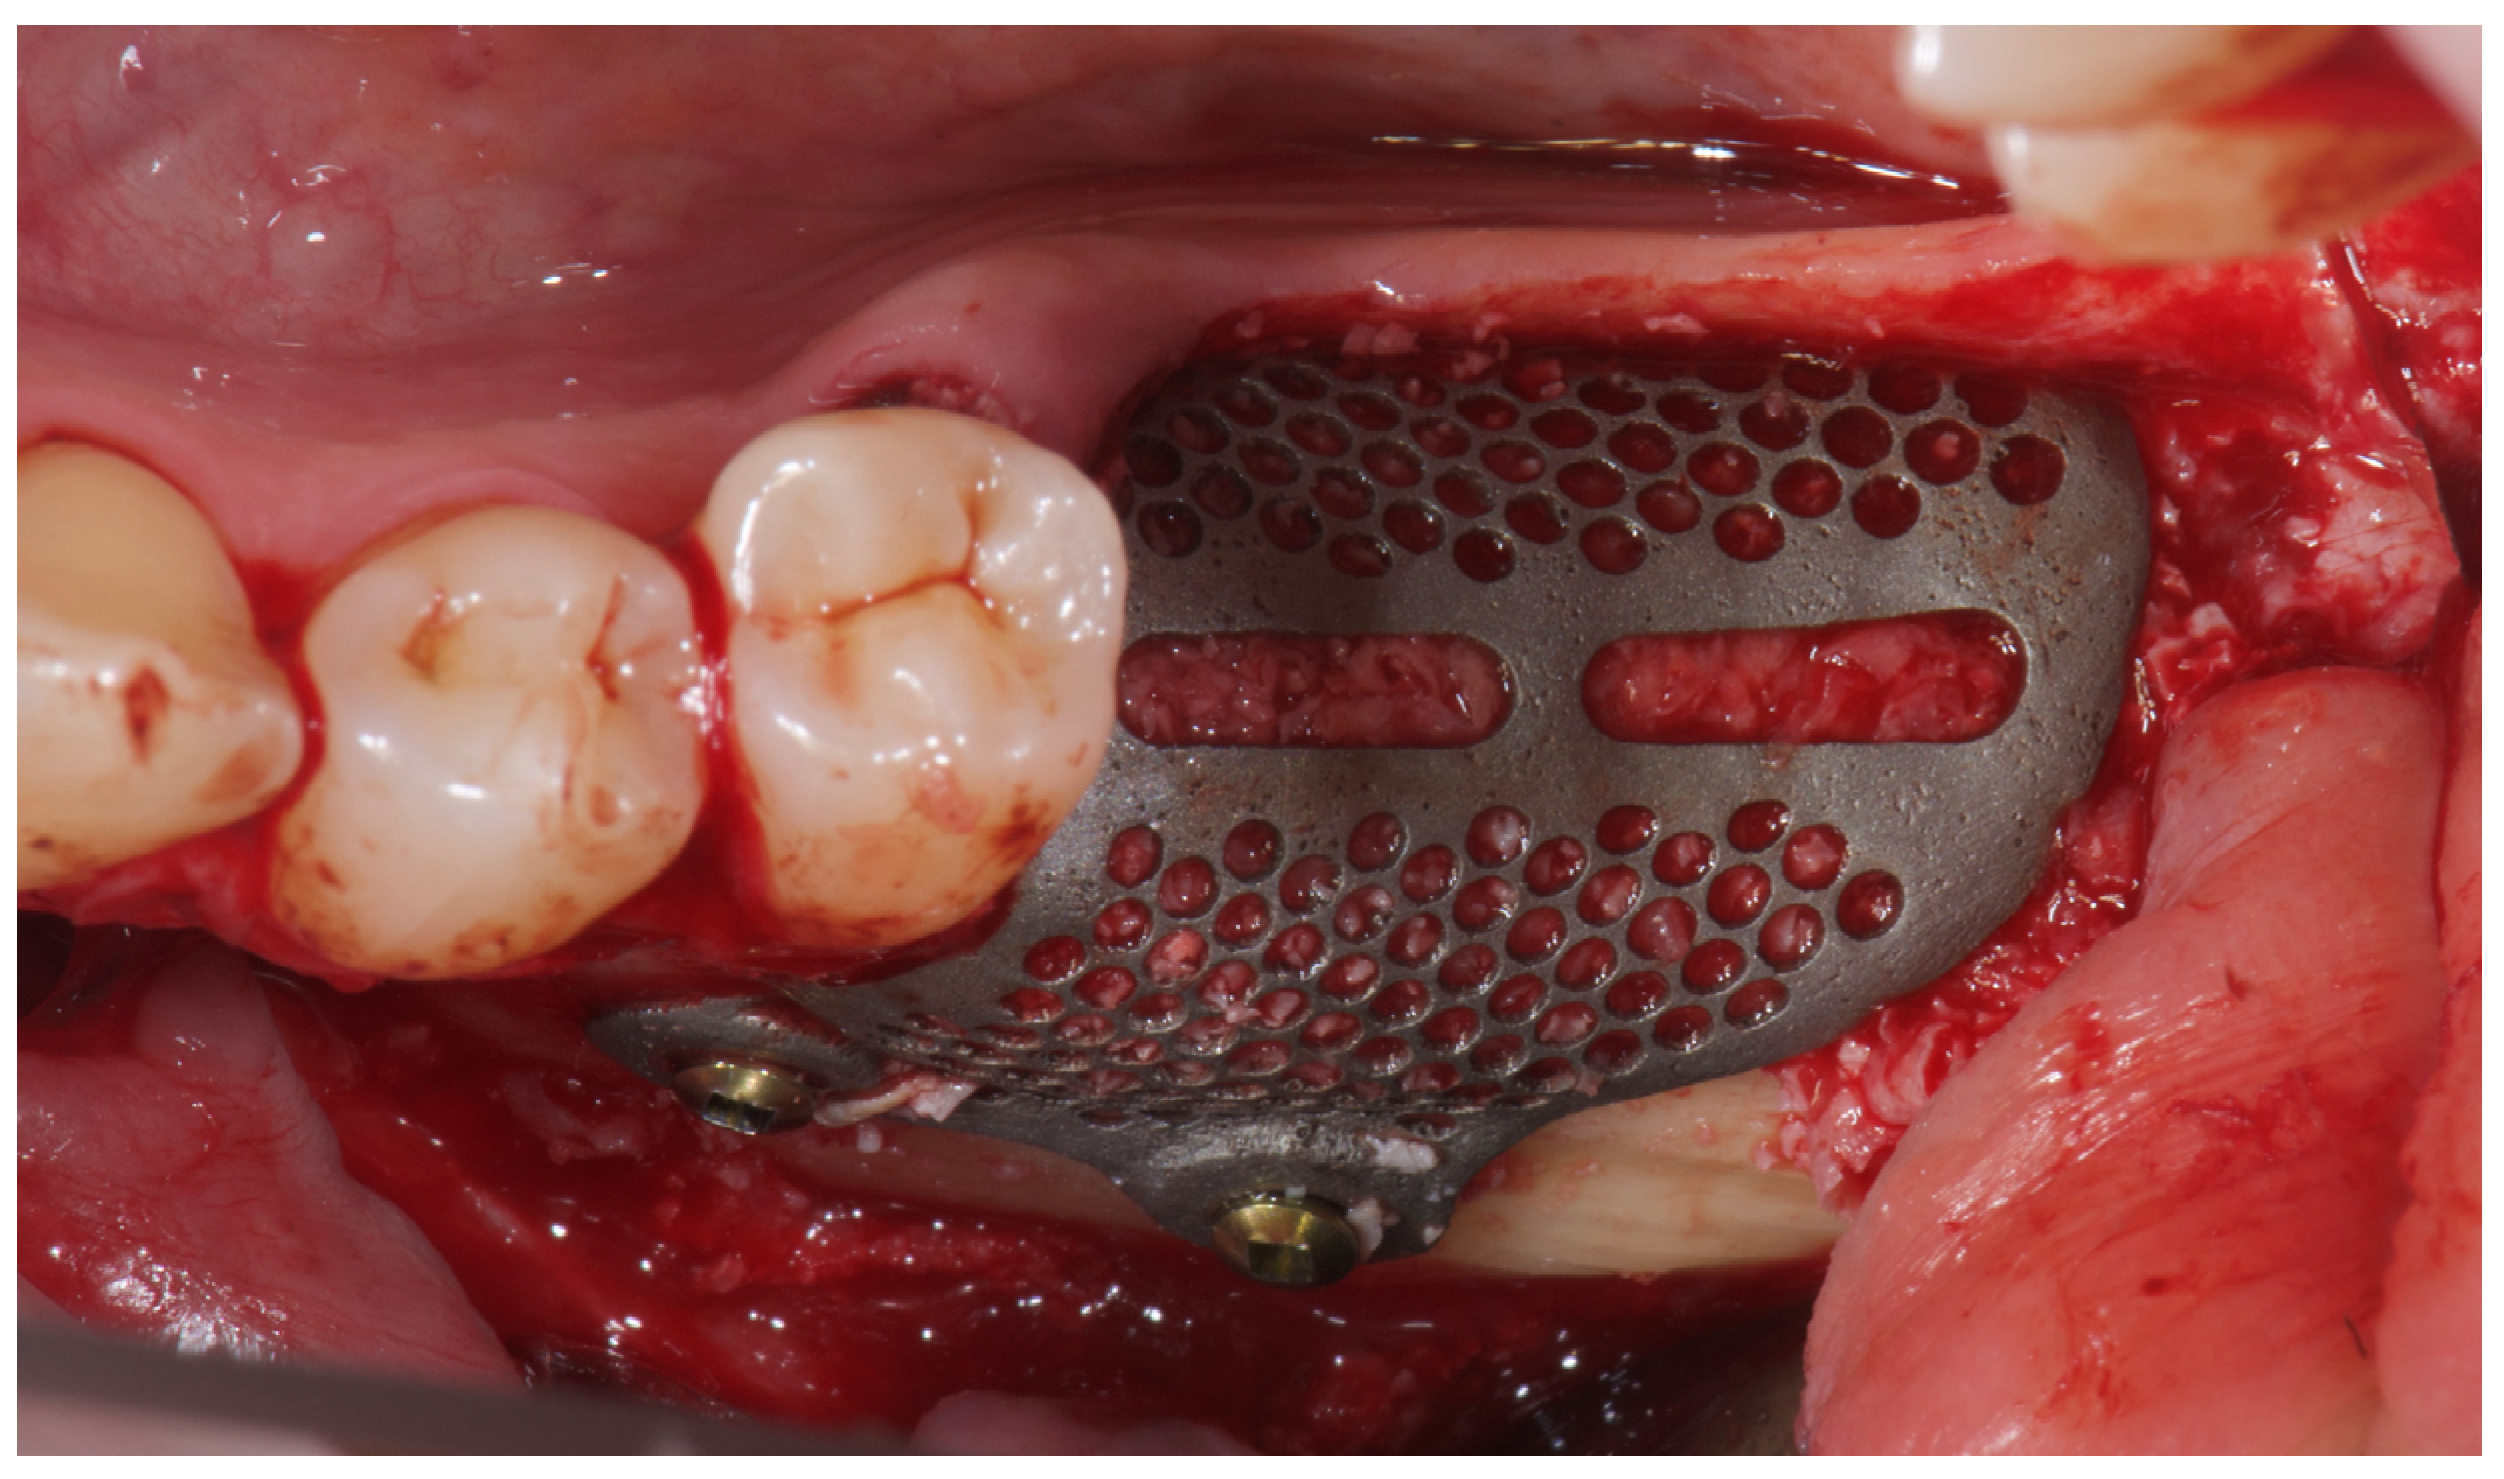

2. Case Summary